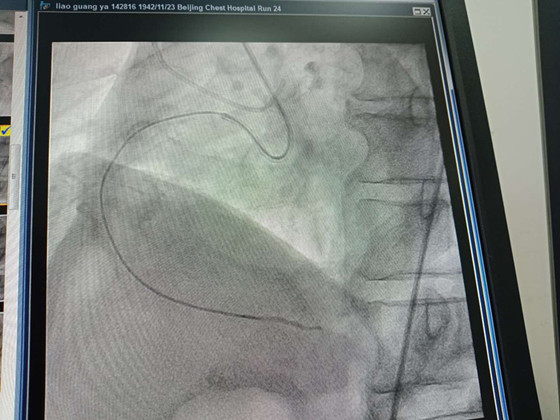

廖教授初次问诊时,只是说当地医生诊断左冠严重狭窄,右侧冠脉问题不大。但当张健看到患者的影像资料时,他发现问题非常严重:老人的右冠脉已经完全堵塞,以致于造影资料中,这条血管已经完全消失了!

在这张术前造影里,患者的右侧冠脉消失了。

他重新为老人做了检查,发现右侧冠脉为严重CTO。

CTO的意思是指冠状动脉的慢性闭塞,闭塞时间在3个月以上,是世界公认的冠脉介入治疗的难题。左侧病变主要表现为左主干严重狭窄、钙化、迂曲,由于右侧血管不通,左主干承担了右侧血管10%的功能。

2小时43分,清晰的血管造影轨迹出现在屏幕上,打通了!血管重建成功!

接下来,3条支架顺利植入老人体内,血流就像被拦截的水库的洪流,瞬间开闸,欢快地喷涌而来,迫不及待的进入老人的心肌,分布在心肌中的毛细血管像被点燃的火把,照亮了整个显示屏。